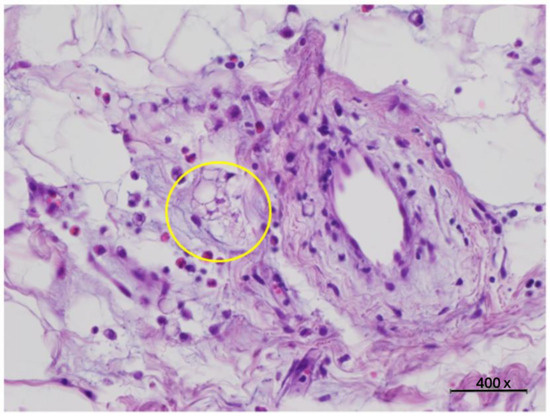

Histology

| Small | (<50 µm) | 10% |

| Medium | (50–69 µm) | 15% |

| Large | (70–89 µm) | 45% |

| Very large | (>90 µm) | 30% |